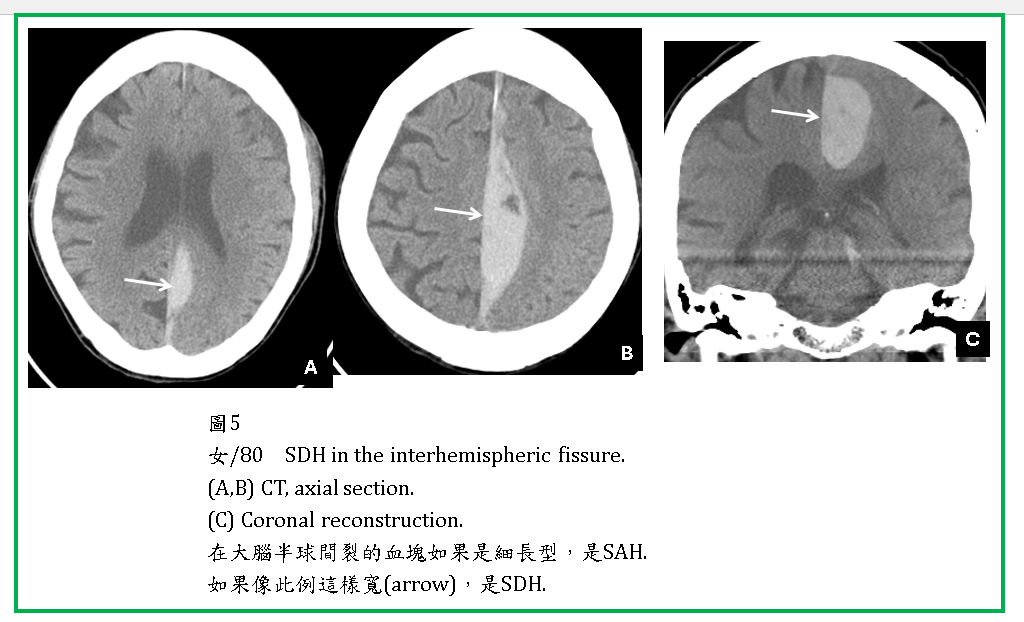

ASDH有時往後會延伸到小腦天幕下的硬腦膜下腔(圖1-3)。在CT橫切面,小腦天幕下SDH呈現片狀,極易被誤為是腦內血塊(ICH) (圖3,4)。SDH有時會在大腦半球間裂(interhemispheric fissure) (圖5),或由大腦額頂葉外的SDH滲透進入interhemispheric fissure 。